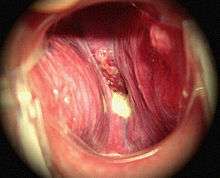

- Presbylarynx is a condition in which age-related atrophy of the soft tissues of the larynx results in weak voice and restricted vocal range and stamina. Bowing of the anterior portion of the vocal folds is found on laryngoscopy.

- Ulcers may be caused by the prolonged presence of an endotracheal tube.

- Polyps and nodules are small bumps on the vocal folds caused by prolonged exposure to cigarette smoke and vocal misuse, respectively.

- Two related types of cancer of the larynx, namely squamous cell carcinoma and verrucous carcinoma, are strongly associated with repeated exposure to cigarette smoke and alcohol.

- Vocal cord paresis is weakness of one or both vocal folds that can greatly impact daily life.